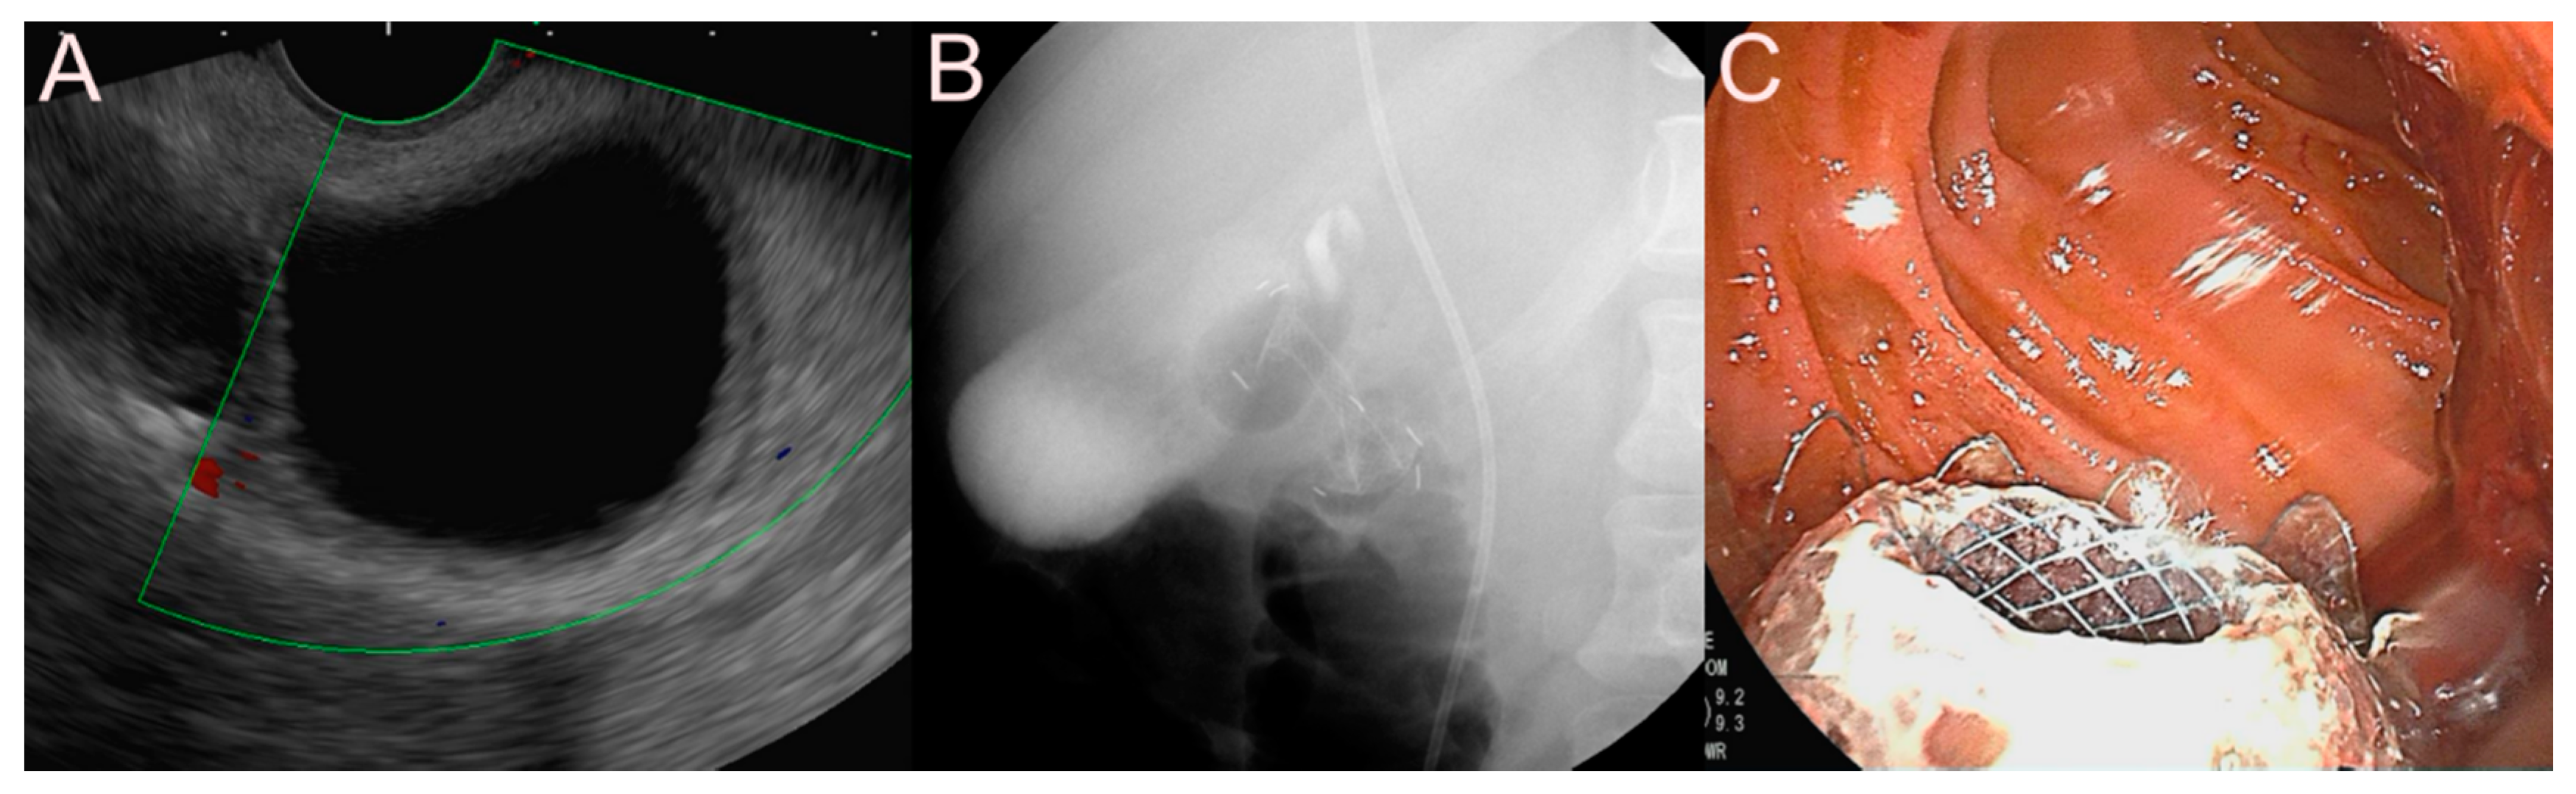

2.1.3. Use of the Lumen-Apposing Metal Stent (LAMS)